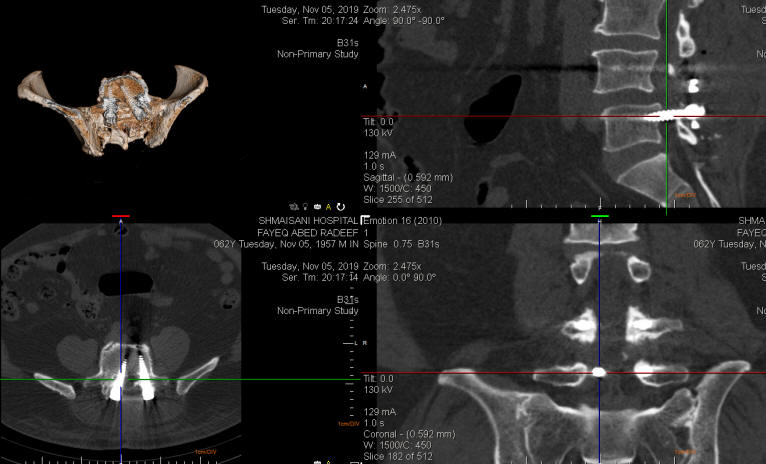

06-NOVEMBER-2019  FAEQ ABDEL-HAMEED RADEEF  63 YEARS  MALALIGMENT OF THE LOWER RIGHT SCREW AFTER TRANSPEDICULAR FIXATION.

The patient was operated by me 02-November-2019 for transpedicular fixation. The patient was diabetic and the power of the right foot improved and due to oozing of the wound the discharge was delayed. The patient was telling that there is still LBP and check X-ray was OK. CT-scan of the spine after reconstructing it with ORS Visual, showed the lower right screw in unacceptable position, for what revision of this screw was mandatory. See the fig-1 below.

Fig-1: the right lower screw is in unacceptable position.

Fig-2: The screws in perfect position after correction.